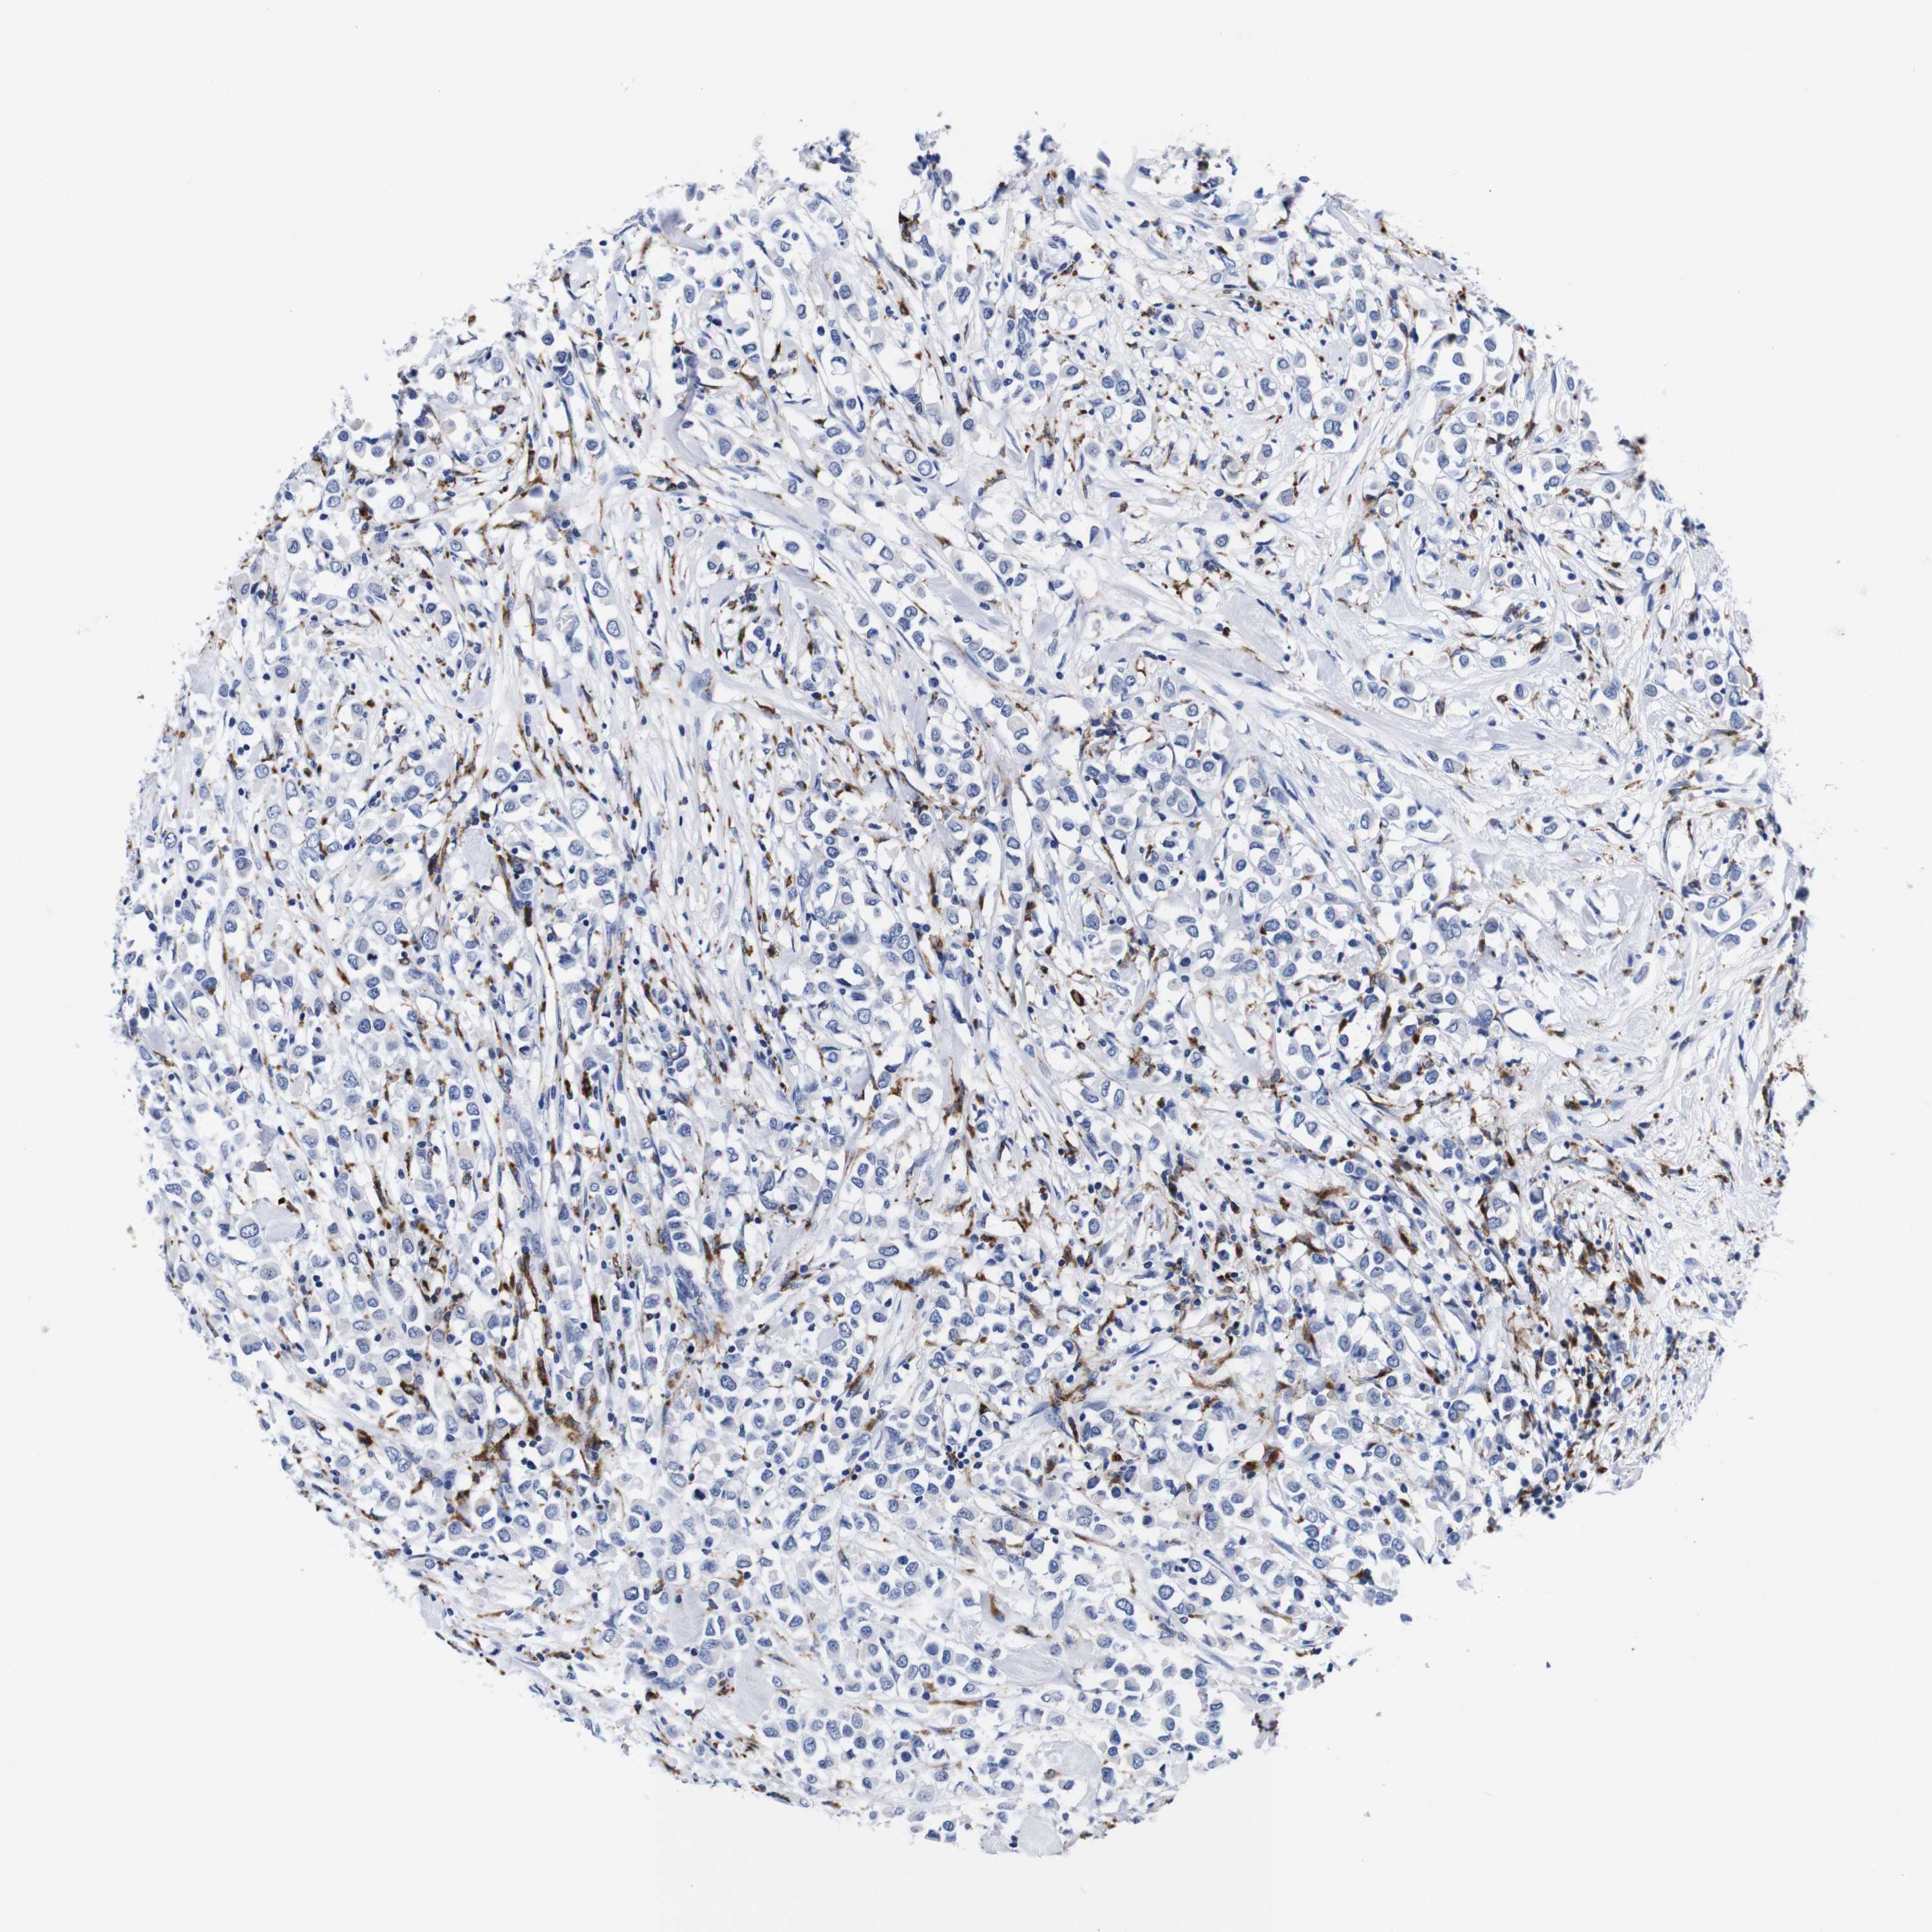

CANCER BREAST CANCER Show tissue menu

BRCA TCGA BRCA VALIDATION PROTEIN EXPRESSION